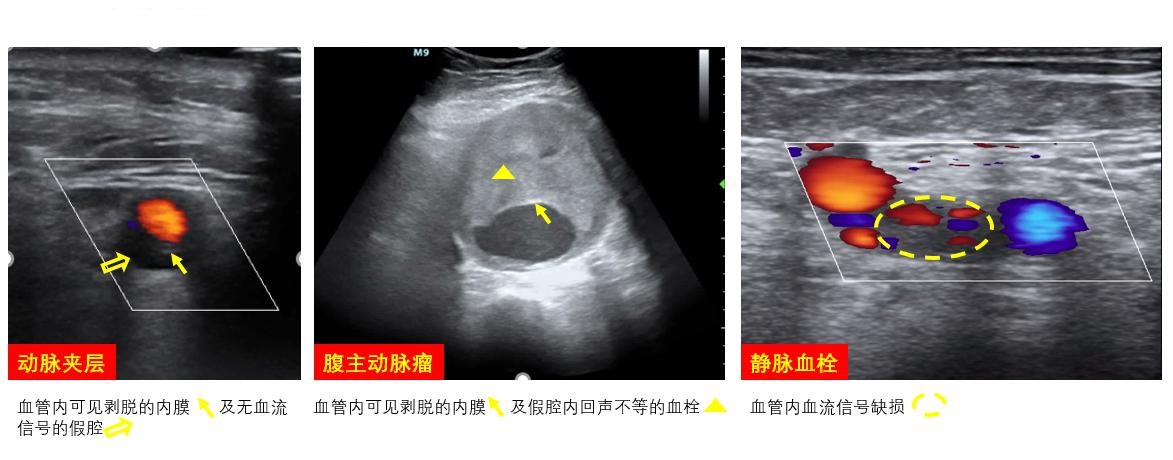

A、不宜穿刺情况拟穿刺动脉穿刺部位及血液回流段血管有严重斑块、钙化、夹层、动脉瘤、动静脉瘘,穿刺点近心端管腔狭窄等(图 10)。若双侧股动脉穿刺均不可行时,可选择右颈总、锁骨下、腋等其他动脉置管通路或中心置管途径进行ECMO支持。

| 图 10 不适宜置管的血管病变 |

2.2 血管对ECMO患者置管血管进行每日常规床旁超声扫查,有助于早期发现操作后血肿、血栓等并发症,以便调整抗凝策略。主动脉血流多普勒形态可协助确定心脏和ECMO血流对流平面。对置管动脉远端肢体的灌注血流进行超声探查,协助明确远端灌注管留置时机和必要性。对已留置侧枝灌注管的远端动脉如股浅动脉、腘动脉、足背动脉等进行血流速连续探测,可协助评估灌注流量大小及变化,及早发现灌注管血栓(图 19)。目前尚无ECMO动脉置管后远端缺血超声预测指标,但仍推荐超声对血管进行每日监测、前后对比,以便早期发现缺血的证据。

血栓也是ECMO常见的并发症之一。由于穿刺损伤血管内皮、血流受阻、血管内置管等多种因素同时存在,对ECMO患者血栓监测不可或缺,超声可对置管血管进行血栓筛查,协助①制定抗凝;②血小板管理策略;③制定拔管计划;④预防血栓脱落避免造成更严重的栓塞并发症。

4 撤机后监测ECMO患者撤机后,仍需利用床旁超声对穿刺血管和穿刺部位进行并发症筛查,包括置管血管的血栓,穿刺部位动脉瘤、动静脉瘘等(图 28)。其余包括原发病的脏器功能监测和重症支持相关即时超声扫查内容则根据患者进行个体化选择,与其他重症患者无异。

| 图 28 置管后并发症 |